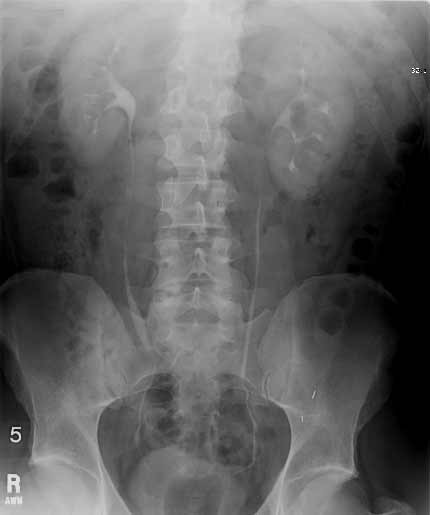

IVP at 5 minutes

Note: Images are shown for illustrative purposes. Do not attempt to draw conclusions or make diagnoses by comparing these images to other medical images, particularly your own. Only qualified physicians should interpret images; the radiologist is the physician expert trained in medical imaging.